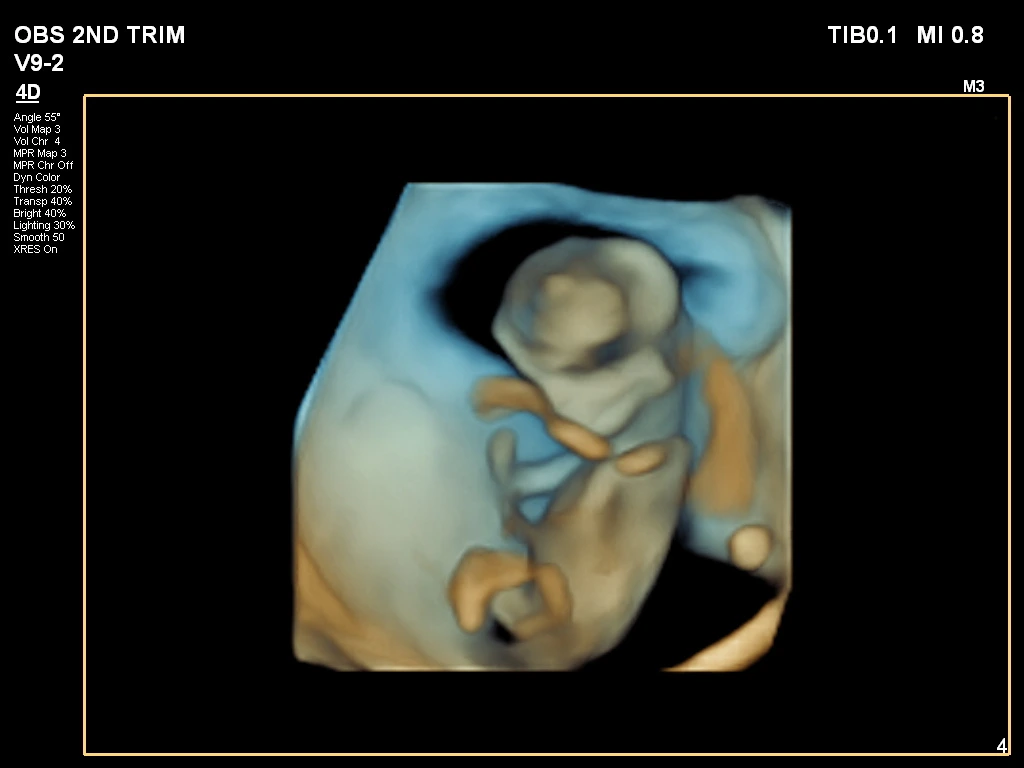

🔹 3D / 4D Ultrasound

3D/4D Ultrasound provides a clear and real-time view of your baby inside the womb. While 3D shows detailed images, 4D allows you to see live movements like smiling or yawning. It enhances bonding between parents and baby while also helping doctors assess physical development. Experience advanced 4D ultrasound in Kathmandu for a memorable and informative pregnancy journey.